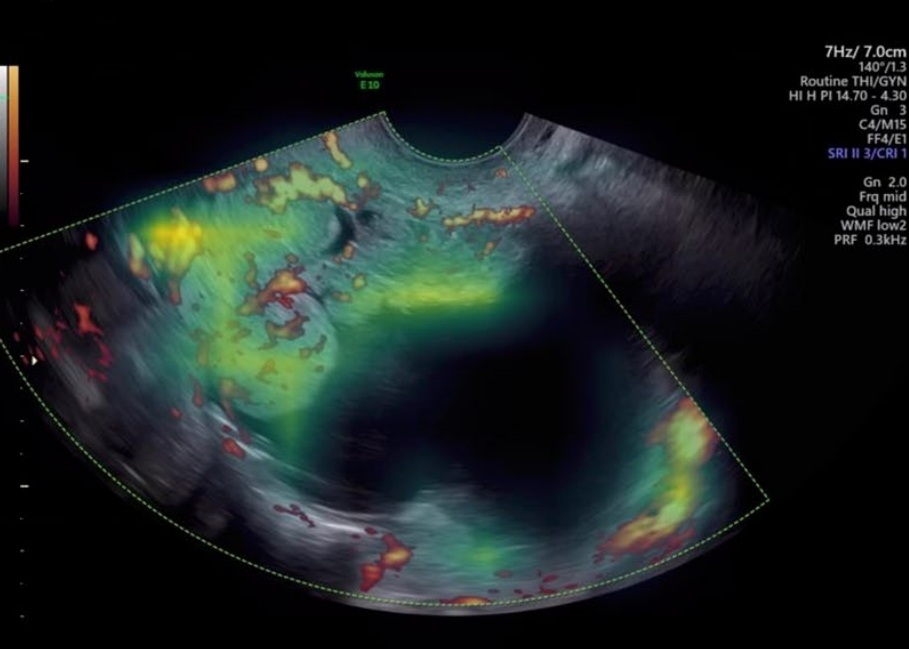

卵巢肿瘤是一种常见的病变,通常在开展其它检查时被偶然发现。超声检查是区分卵巢病变良恶性的主要技术手段,其检查结果极大程度上决定了治疗措施。然而,即使是在发达地区,经验丰富的超声检查人员依旧处于短缺状态,这导致误诊、漏诊时有发生。

目前,基于深度学习开展的超声图像卵巢病变辅助诊断技术已展现出积极的成果,但仍需充分的外部验证提供佐证。Nature Medicine近期基于Transformer开展了一项国际多中心回顾性研究,方法不算复杂,比较适合用作入门学习的技术路线。

该研究使用了8个国家、20个中心、3652名患者的17119张超声图像,涵盖了9个制造商的21种超声系统。该研究基于预训练的Transformer模型,通过留一中心交叉验证方案开展卵巢病变辅助诊断研究,展现了强大的泛化能力以及媲美资深检查人员的诊断准确性。